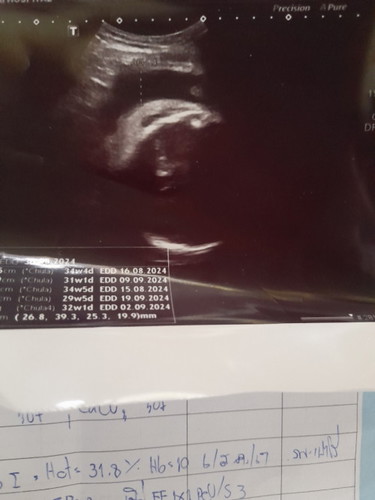

ในอันตร้าซาวใบนี้สามารถดูเพศได้ไหมคะ

ดูไม่ออกค่ะแม่นี่คือส่วนไหนค่ะ